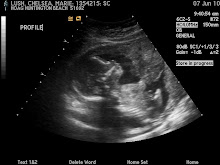

| Introduction | I am a 21 year old mom. Married to my best friend. I love Jesus, my family, and bonding with Zoe, my beautiful daughter with osteogenesis imperfecta. |